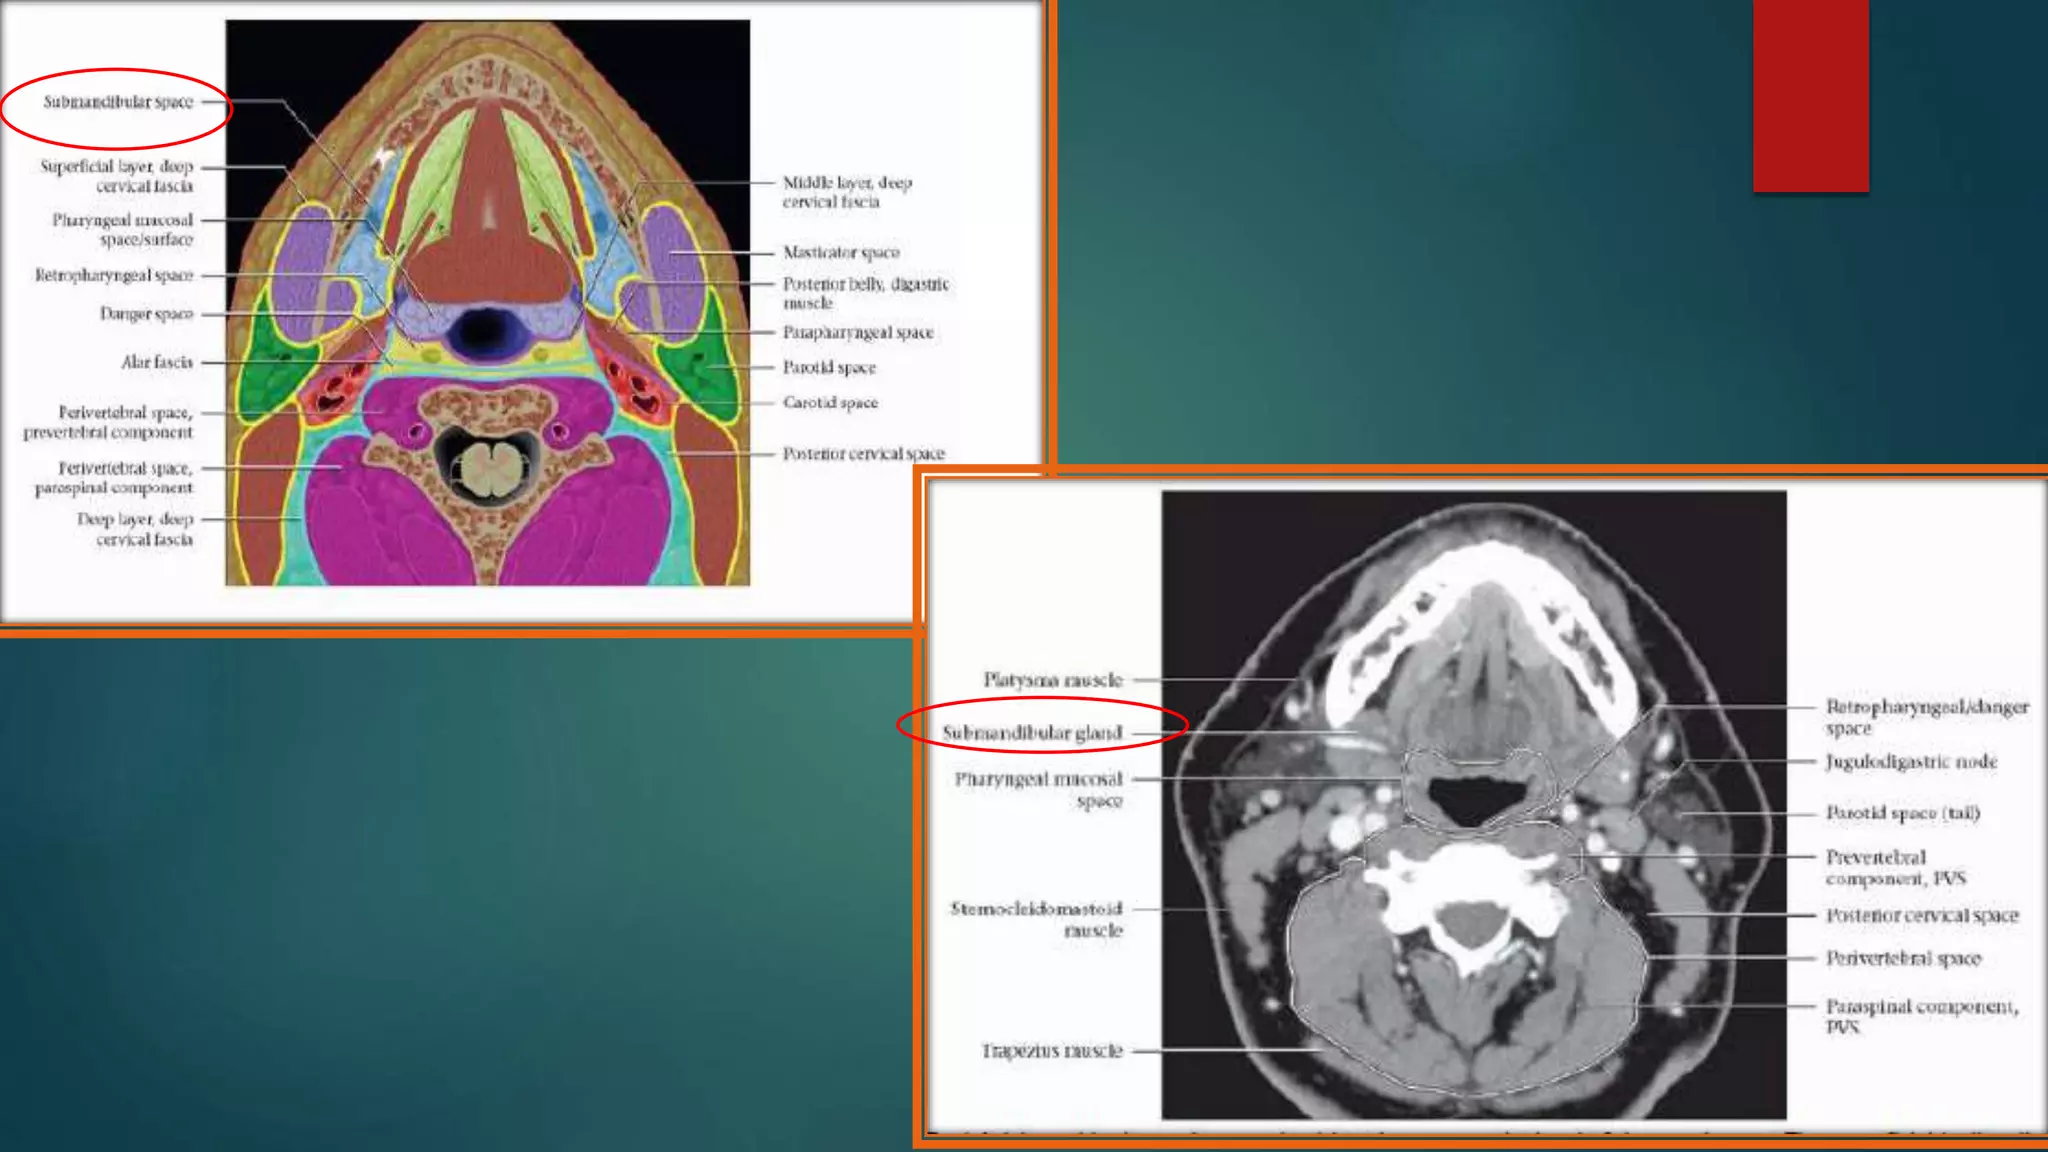

SUBMANDIBULAR SPACE

 Extend : Mylohoid superiorly & hyoid

bone inferiorly.

 Communicates freely with sublingual

space.

 Contents : superficial portions of the

Submandibular gland, submental and

submandibular LNs, facial artery and

vein, fat and ant belly of digastric.